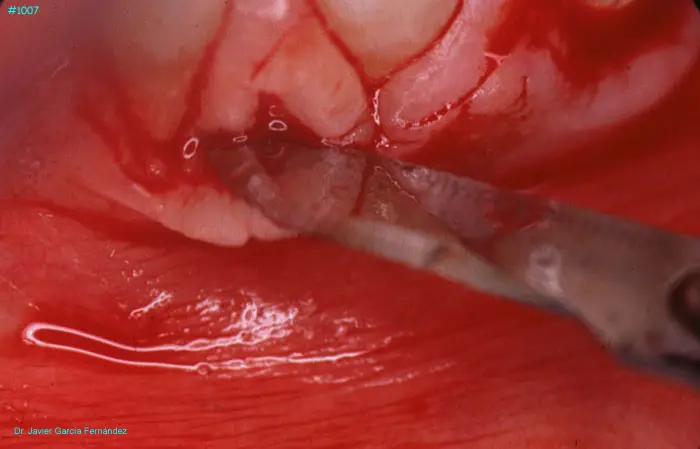

Atlas of Surgical Techniques in Periodontics. Chapter III. Atlas de Técnicas Quirúrgicas en Periodoncia